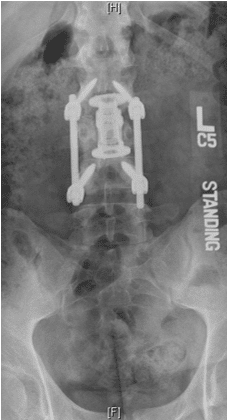

Surgery

Patient was operated and the spinal canal cleaned up of all bony fragments. The spine was fixed from the side and the back to take care of instability.